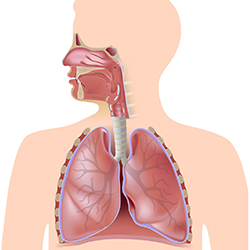

When do kids develop allergies?

Seasonal allergies can start at almost any age, though they usually do not develop before a child is 2 years old.

What helps asthma cough in children?

Your child's quick-relief (rescue) medicine. Start it at the first sign of any wheezing, shortness of breath or hard coughing.

Can a child with cystic fibrosis live a normal life?

Most people with cystic fibrosis live a normal daily life, with the challenge of incorporating daily medications and other treatments.

How do I know if my child has

pneumonia?

Common symptoms such as Cough, vomiting, diarrhea, loss of appetite, tiredness and fever could be visible

in your child frequently